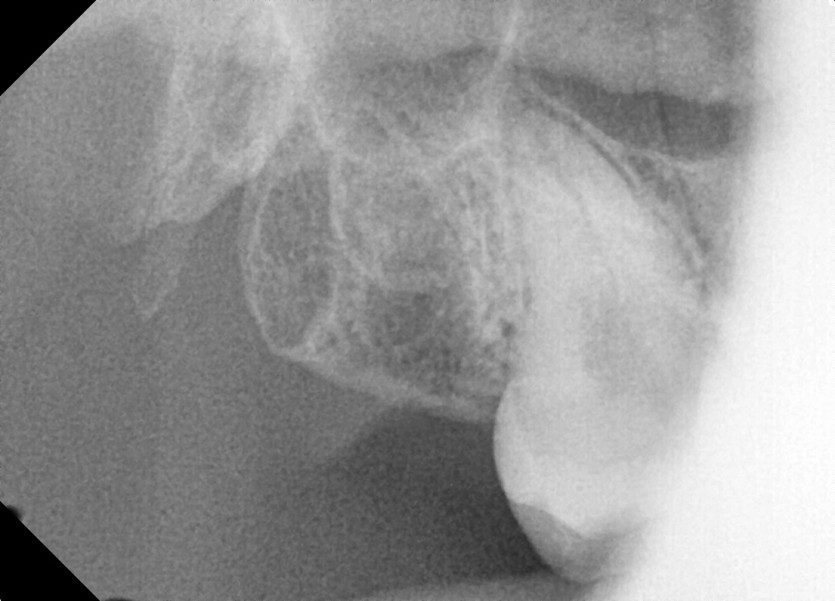

#18,48 사랑니 발치

구강외과 전문의가 당일발치 했습니다.